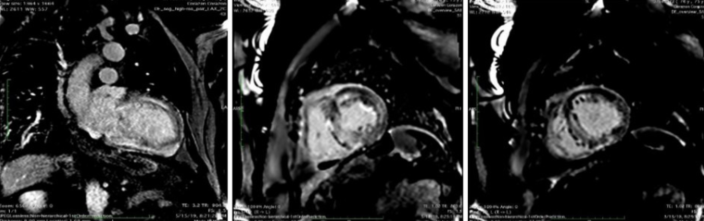

- Cardiorresonancia, que muestra (figura 1) un ventrículo izquierdo dilatado con HVI a predominio septal de 22 mm, hipoquinesia global, función global disminuida leve a moderada de 43%, dilatación biauricular moderada. Ventrículo derecho con disminución de su función, fracción de eyección del ventrículo derecho (FEVD) de 47%. En la secuencia de T2 no presentaba edema. La fase de perfusión fue normal. El realce tardío muestra dificultad en anular el miocardio característico de la amiloidosis, realce tardío global transmural presentó un patrón heterogéneo, de distribución no vascular respetando parcialmente el subepicardio anterior basal y medio y septal basal. Se trata de un estudio compatible con amiloidosis cardíaca.

Cardiorresonancia que muestra el realce tardío con gadolinio intramiocárdico y transmural difuso, típico de amiloidosis cardíaca.